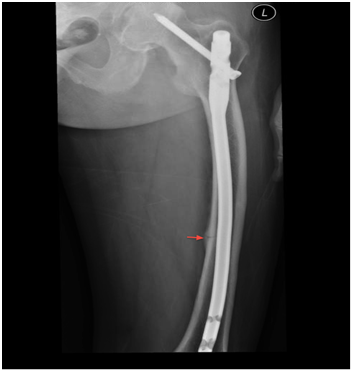

A skeletal survery performed during the hospital stay showed findings consistent with osteomalacia including arrest lines (distal femur and proximal tibia in Figure 3), looser’s zones (shaft of femur in Figure 4), frontal bossing (Figure 5) and multiple endplate compression deformities in the thoraco-lumbar spine (Figure 6).

Figure 4 Shaft of femur showing bowing and arrow pointing the looser’s zone.